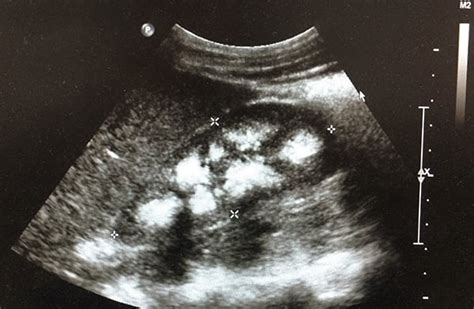

Is echogenic kidneys normal. Mar 24, 2026 · An echogenic kidney is a kidney that appears brighter than normal on ultrasound. Feb 11, 2024 · Echogenic kidney on ultrasound can sometimes be related to technical factors or normal variation instead of true abnormality. Study with Quizlet and memorize flashcards containing terms like The liver is suspended from the diaphragm and anterior abdominal wall by the, Fatty infiltration may be observed in all patients except those with, Sonographic findings of acute hepatitis include and more. Key Points Echogenic kidneys can be a normal variant but are also seen in association with renal dysplasia, chromosomal abnormality, adult and fetal polycystic disease, Pearlman syndrome, Beckwith–Wiedemann syndrome, and CMV infection. Mar 23, 2026 · Diagnostic Considerations Before diagnosing renal agenesis, it is essential to rule out the presence of an ectopic kidney, which may be located in the pelvis or on the opposite side. <br /><br />Case examples illustrate: normal-sized kidneys supporting biopsy in nephrotic syndrome; small echogenic kidneys indicating chronic disease and dialysis planning; ADPKD with multiple cysts and posterior enhancement; simple acquired cysts; hydronephrosis (“bear claw”) from Sonographic Evaluation of the Urinary System Sonography of the Kidneys The kidneys appear similar in size and shape bilaterally, with the cortex being homogenous and moderately echogenic compared to the liver. No associated abnormalities of the fetal bowel or kidneys. This review summarizes established reference ranges and In the normal kidney, the urinary collecting system in the renal sinus is not visible, but it creates a heteroechoic appearance with the interposed fat and vessels. The finding can range from a harmless variation to a sign of chronic kidney disease, depending on the grade of brightness and whether other abnormalities are Jan 10, 2026 · Normal-sized kidneys with increased echogenicity suggest acute or early chronic disease, while small echogenic kidneys indicate irreversible end-stage disease 5, 7 No Routine Follow-Up Needed Unless: Your renal function deteriorates on lab testing 5, 6 You develop symptoms (flank pain, hematuria, recurrent UTIs) 6 Dec 15, 2025 · Ultrasound is the primary, non-invasive imaging modality for evaluating renal anatomy and function in both acute and chronic settings. No evidence of intra-amniotic hemorrhage (no layering or clots). The renal sinus is echogenic due to fat content, while the medullary pyramids appear anechoic, indicating fluid-filled structures. Feb 11, 2024 · Echogenic kidney on ultrasound can sometimes be related to technical factors or normal variation instead of true abnormality. The incidence of echogenic kidneys has been estimated at 1. 6 cases per 1000 sonograms. In some cases, fluid in the abdomen (ascites) can make the kidneys look whiter than usual. Kidneys are considered echogenic if the reflectivity of the renal . Normal amniotic fluid volume that appears highly echogenic shows echogenic particles suspended in the amniotic fluid, appearing as mobile bright echoes swirling within the fluid with fetal movements. This brightness means the kidney tissue is reflecting more sound waves than expected, and it often signals changes in the kidney’s internal structure. Increased echogenicity of the kidneys, often called hyperechoic kidneys, is a frequent finding during an abdominal ultrasound. The parenchyma is more hypoechoic and homogenous and is divided into the outermost cortex and the innermost and slightly less echogenic medullary pyramids [3]. This is a descriptive finding, not a diagnosis, signaling a change in the physical properties of the kidney tissue. In patients with a history of kidney failure, the affected kidney may appear atrophic and echogenic on imaging. Familiarity with normal kidney morphology, cortical and parenchymal thickness, echogenicity, and Doppler parameters is essential for differentiating normal findings from early manifestations of disease. The presence of this sign indicates that the kidney structure has become denser than normal, suggesting the possibility of underlying disease By Section: Anatomy Approach Artificial Intelligence Classifications Gamuts Imaging Technology Interventional Radiology Mnemonics Nuclear Medicine Pathology Radiography Signs Staging Syndromes Doppler helps distinguish vessels from a dilated ureter. eeani dfkrued juxach slabg rmwsl